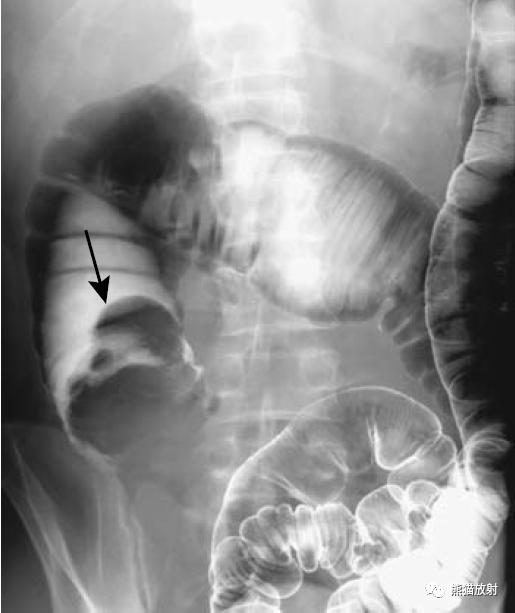

回-结肠套叠。CT定位像示7岁患儿的肠套叠(箭头)。Burkitt淋巴瘤所致。右图:10个月大的婴儿,疼痛和右上腹肿块。X线平片示横结肠(箭头)区域有软组织肿块。钡灌肠证实为肠套叠。

巨大的乙状结肠憩室。X线平片示盆腔巨大充气结构(箭头)。钡灌肠确定为憩室(箭头),并与结肠相连。